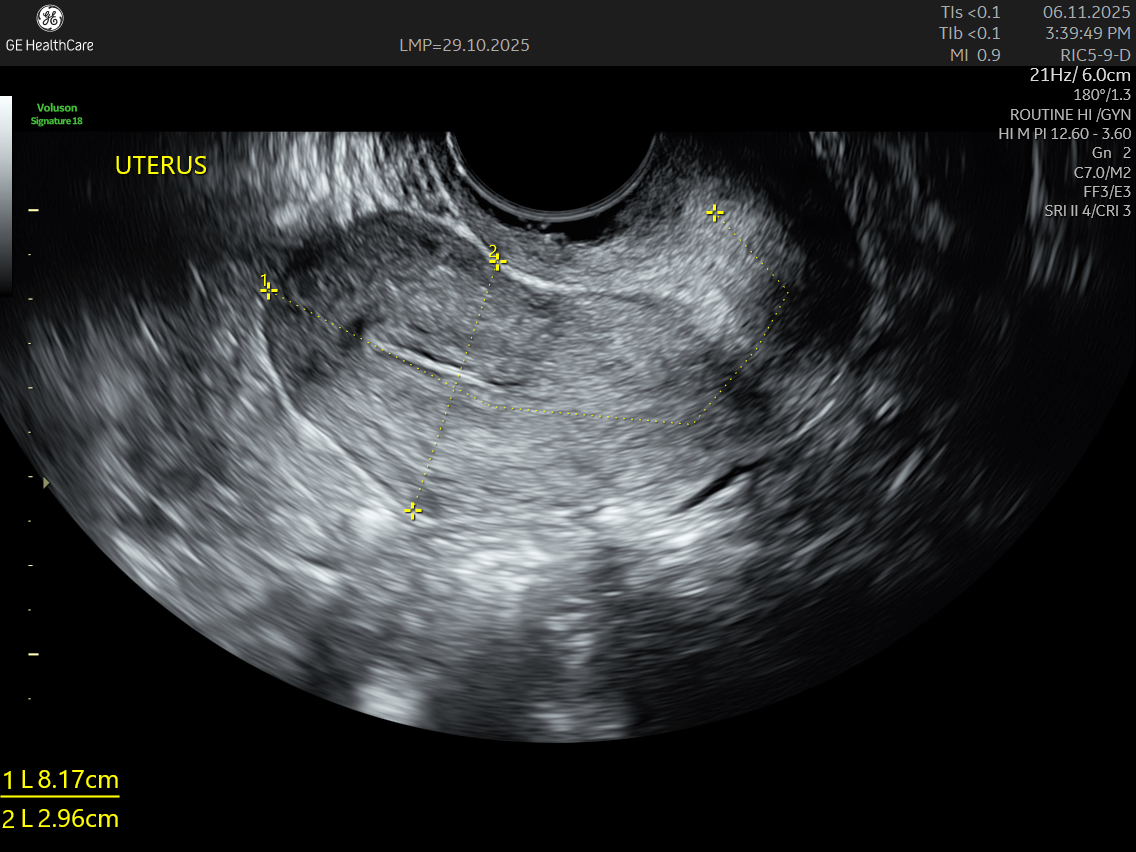

Saline Infusion Sonography (SIS), also known as saline sonohysterography, is a specialized ultrasound that provides a clearer and more detailed view of the uterine cavity. A routine scan uses ultrasound waves for visuaising th internal organs. A special USG transducer detects the echoes from the waves that bounce off the surface of the organs and soft tissues. But since the inside of the uterus cavity is filled with fluid, any abnormalities inside the uterine cavity cannot be differentiated in a 2D ultrasound. A SIS involves gently introducing sterile saline into the uterus, which helps highlight the inner lining and reveal even subtle abnormalities.

SIS is a diagnostic ultrasound technique designed to assess the uterus in greater detail. By filling the uterine cavity with a saline solution, the procedure separates the cavity walls and offers a clear contrast during imaging. This allows doctors to identify issues that might be missed on a standard pelvic ultrasound.

IMAGE GALLERY